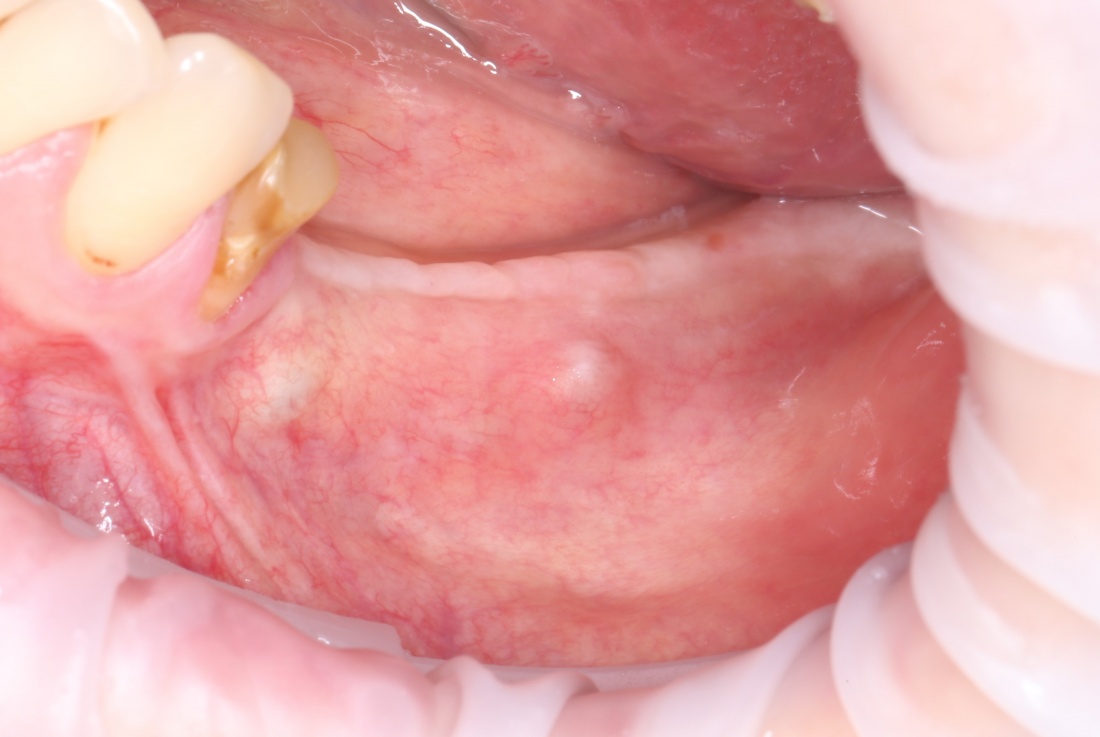

Теперь возьмём клинический случай (нижняя челюсть, отсутствия 35, 36, 37 зубов, атрофия альвеолярного гребня по ширине):

и рассмотрим его через парадигму методологического редукционизма. Или, если хотите, сквозь Бритву Оккама.

Мы имеем относительно небольшой дефект, не позволяющий, однако, установить имплантаты правильного размера в правильное положение. И два варианта остеопластической операции, НКР и АТККФ.